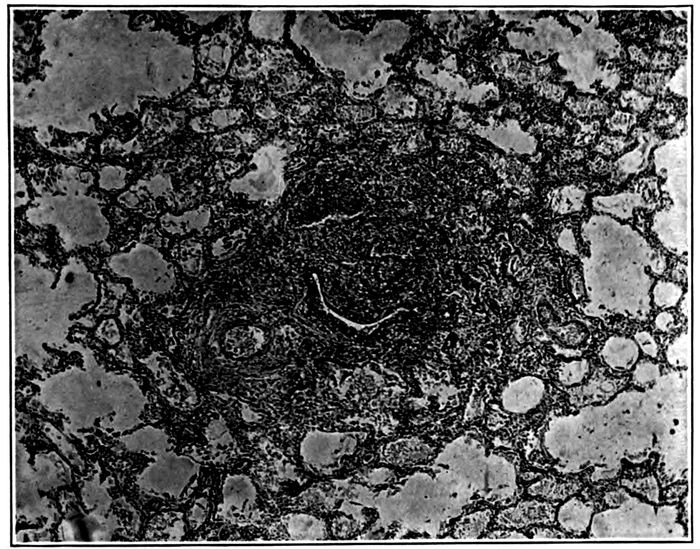

| 2. | Acute bronchopneumonia with nodules of peribronchiolar consolidation and purulent bronchitis | 167 |

| 3. | Acute bronchopneumonia with peribronchiolar consolidation | 169 |